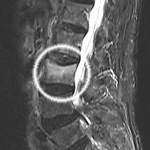

日本が超高齢社会に突入し、骨粗鬆症を有する高齢の方が激増している中、この病態の認識はまだまだ浸透しておりません。早期発見・早期治療開始が必要な疾患であり、早期診断のためにはMRI検査が必要です。

(レントゲン)

(MRI)

レントゲンでは骨折が判り難いがMRI検査により骨折が判別した例